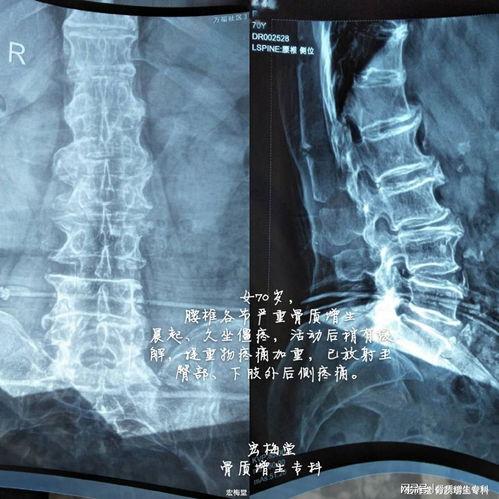

首先,咱们得先弄明白什么是腰椎骨质增生。简单来说,就是腰椎部位的骨头边缘长出了多余的骨刺,这些骨刺会压迫周围的神经和软组织,导致疼痛、麻木等症状。虽然听起来有点吓人,但其实只要通过适当的锻炼,就能有效缓解症状。